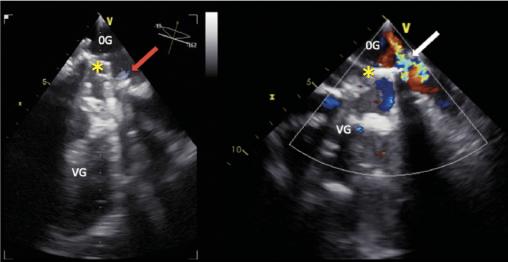

Cette femme de 67 ans avait une asthénie et par intermittence des urines sombres. Une insuffisance mitrale rhumatismale avait été traitée 22 ans auparavant par remplacement valvulaire chirurgical. Le bilan biologique révélait une anémie (7,6 g/dL) normochrome normocytaire régénérative (taux de réticulocytes à 278 000/mm3), un taux de lacticodéshydrogénase à 2 688 UI/L, un taux d’haptoglobine inférieur au seuil de détection et un taux normal de bilirubine totale. Le frottis sanguin (fig. 1 ) notait de très nombreux schizocytes (plus de 500/1 000). L’échocardiographie transœsophagienne (ETO)montrait la présence d’une végétation et une fuite prothétique (fig. 2 ). Il s’agissait d’une endocardite infectieuse à Pseudomonas aeruginosa compliquée d’une désinsertion de valve prothétique.

Les schizocytes, fragments circulants d’hématies, sont caractéristiques de l’hémolyse mécanique, telle que la microangiopathie thrombotique.1 Une hémolyse infraclinique chronique peut être présente en cas de valve prothétique de fonctionnement normal. Son incidence tend à diminuer du fait des améliorations de conception des prothèses.2 Un syndrome anémique ou des stigmates biologiques témoignent d’un dysfonctionnement ou plus fréquemment d’une fuite paraprothétique.3 L’hémolyse résulte de forces de cisaillement en lien avec la turbulence du flux.2 Une fuite paravalvulaire tardive traduit souvent une déhiscence de suture, favorisée par la calcification annulaire ou causée par une infection.3